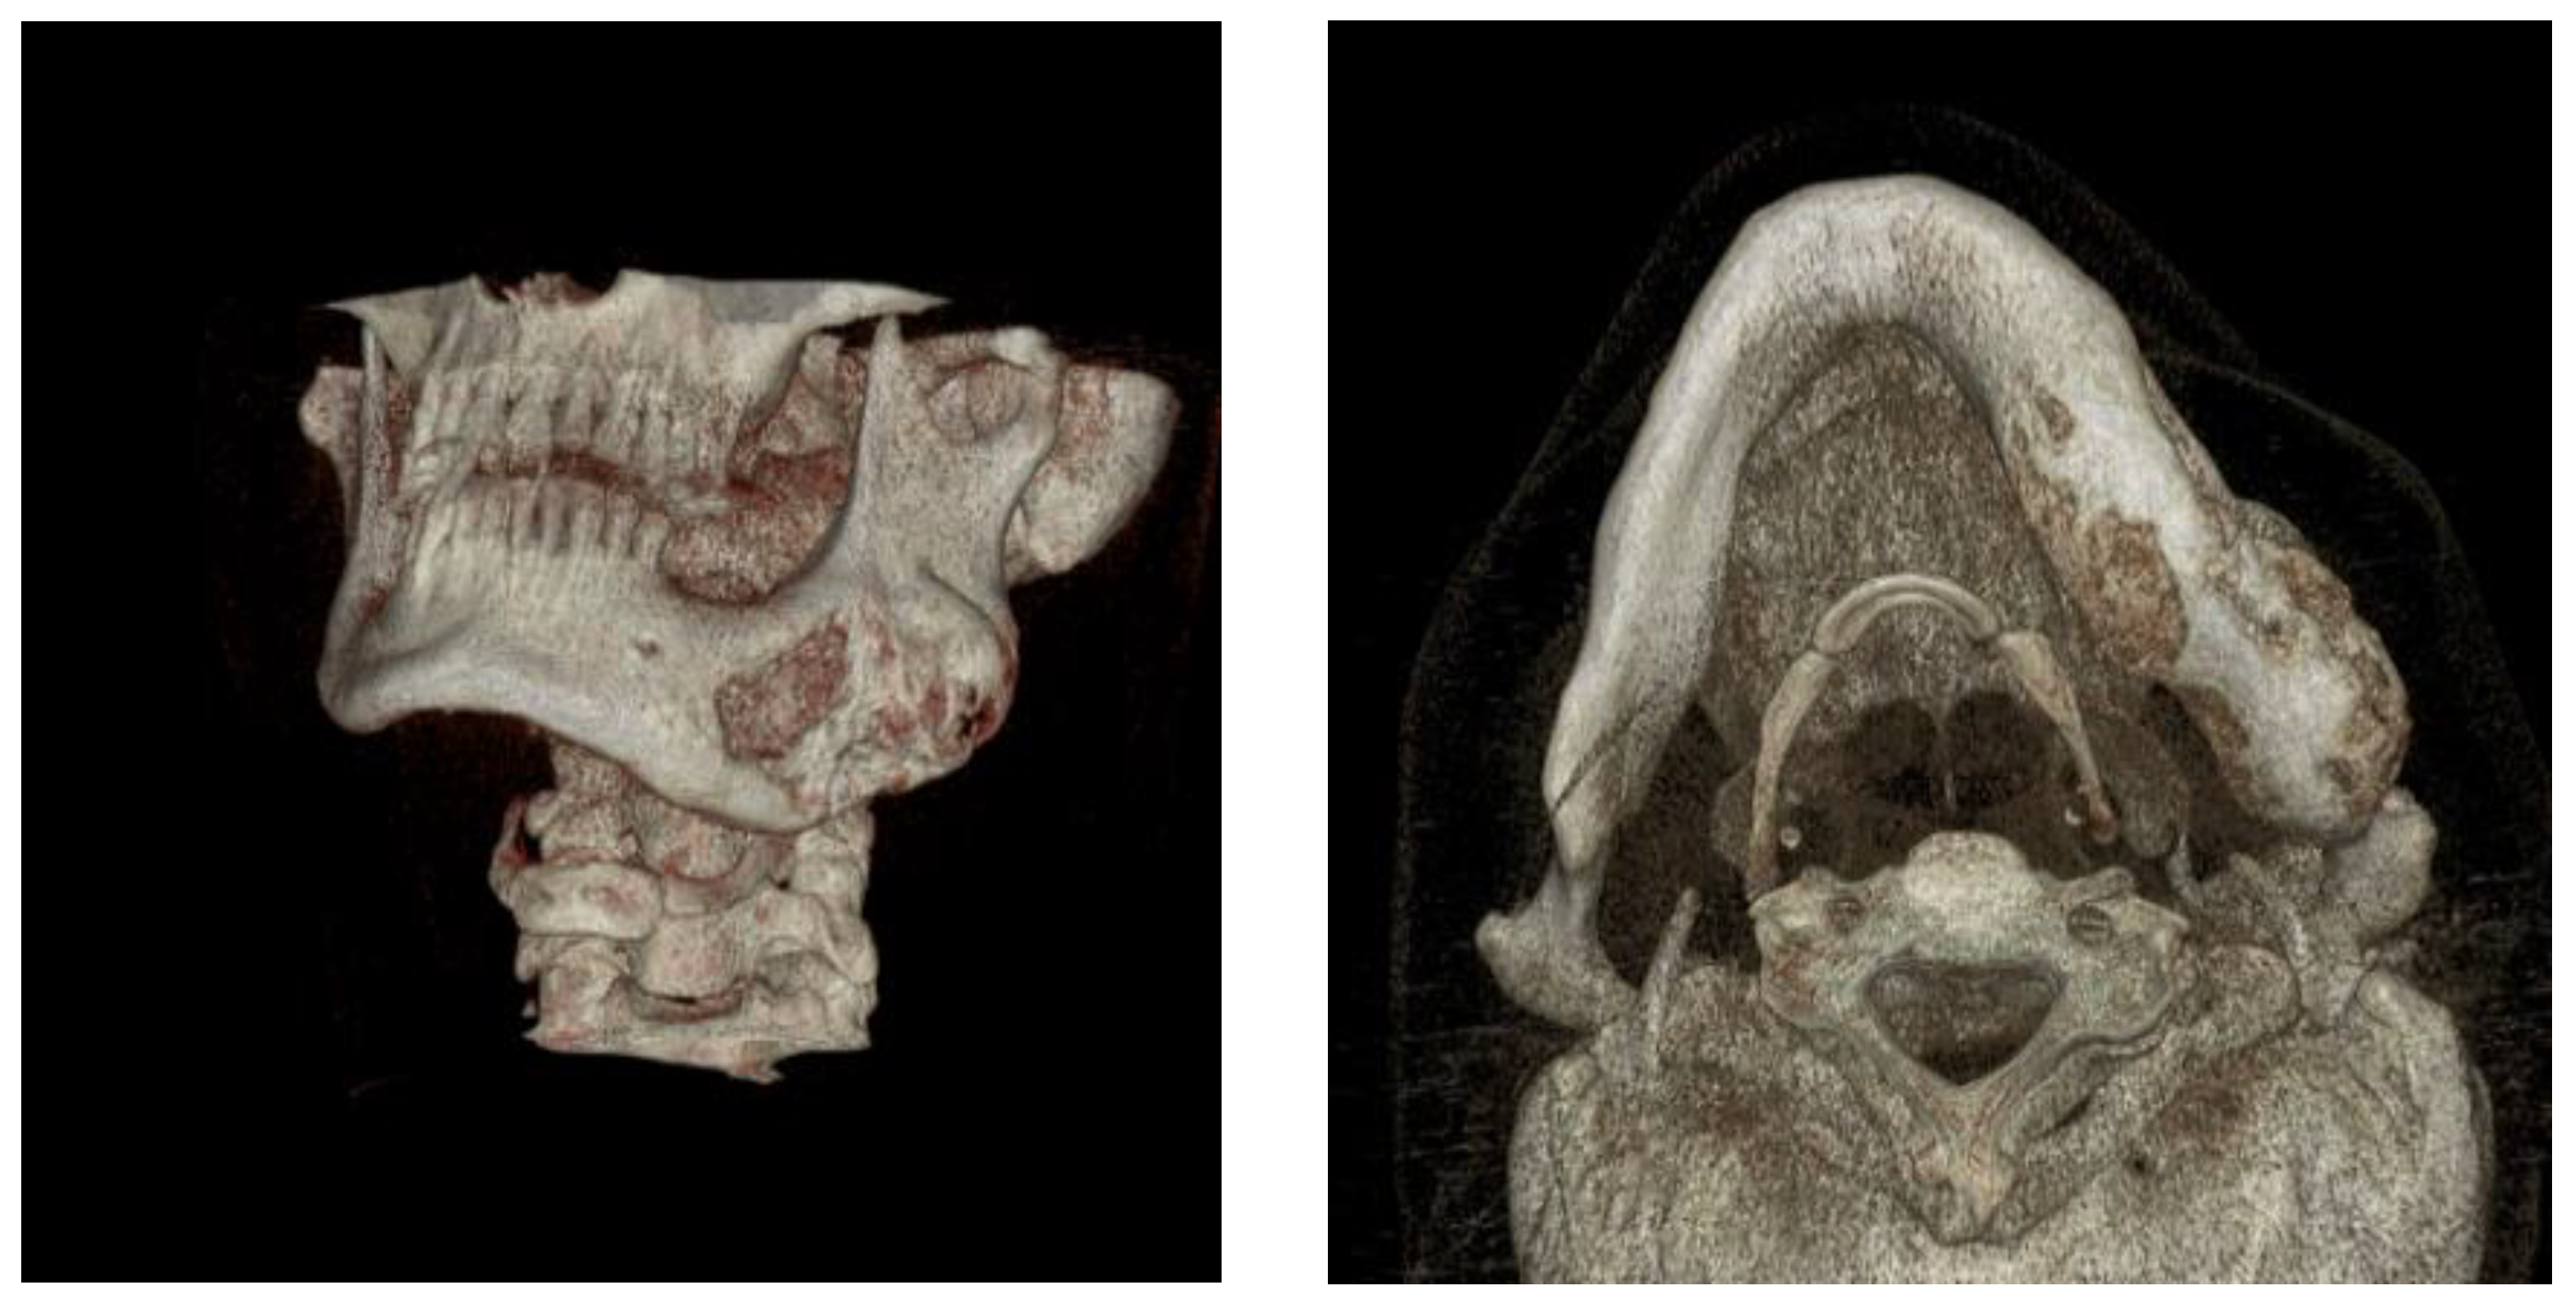

- phase 1: Conversion of the CT scan of the mandible from DICOM format to a 3D STL model

- phase 2: Model of the deformed part of the mandible before and after computer-assisted resection